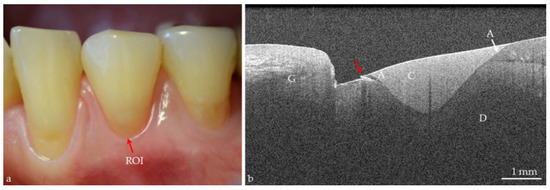

Figure 2. Screenshot, in vivo image of a human incisor. Partial conformance of visual assessment with OCT. A carious lesion (L) of ICDAS II Code 2 can be detected visually at the air-dried enamel surface (red arrow). In the SD-OCT B-scan, this lesion appears as a bright shadowed area without cavitation. Compared to visual assessment, the OCT signal reveals an extended lesion body with dentin (D) involvement and a mineral-rich and porous surface layer (*). In addition, defects, or cracks in the enamel (E) are seen to cause shadowing (white arrows). G: gingiva, EDJ: enamel-dentin junction.

Today the big challenge in caries diagnosis is the detection of very early stages of demineralization, especially in enamel [12,39]. Effective caries management presupposes that these early lesions (represented by porous areas very different in extension) can be reliably recorded. On smooth tooth surfaces, beginning demineralizations can be detected visually as white spot lesions on dried enamel surfaces (ICDAS II Code 1, Figure 1) [3,40], which are a common complication during treatment with fixed orthodontic appliances [41]. At this stage, the subsurface enamel porosity can be stopped or reversed using appropriate non- or minimally invasive therapies and biofilm control [8]. White spot lesions appear whitish as the incident light is backscattered off porous regions to a considerable extent [29,39]. OCT makes use of the same phenomenon. In contrast to the clinical detection solely at the surface, OCT can image structures up to a depth of 2.5 mm and might therefore be a useful supplement to the visual-tactile assessment of tooth surfaces (ICDAS II) and radiography. More reliable differentiation between the really early lesion signs (ICDAS II Codes 0–2) might become possible, irrespective of existing color changes or surface moisture (Figure 1 and Figure 2). Unlike other diagnostic methods, cross-sectional OCT images can present the axial and lateral extension of different demineralized zones (Figure 5).

In vitro studies showed an adequate to strong agreement, when SS- or SD-OCT were compared to histology [29,42,43], confocal microscopy, X-ray microtomography, or transverse microradiography and a diagnostic superiority compared to bitewing radiography [44] (Figure 1, Figure 2, Figure 5, Figure 6, Figure 7, Figure 8, Figure 9, Figure 10, Figure 11 and Figure 14).